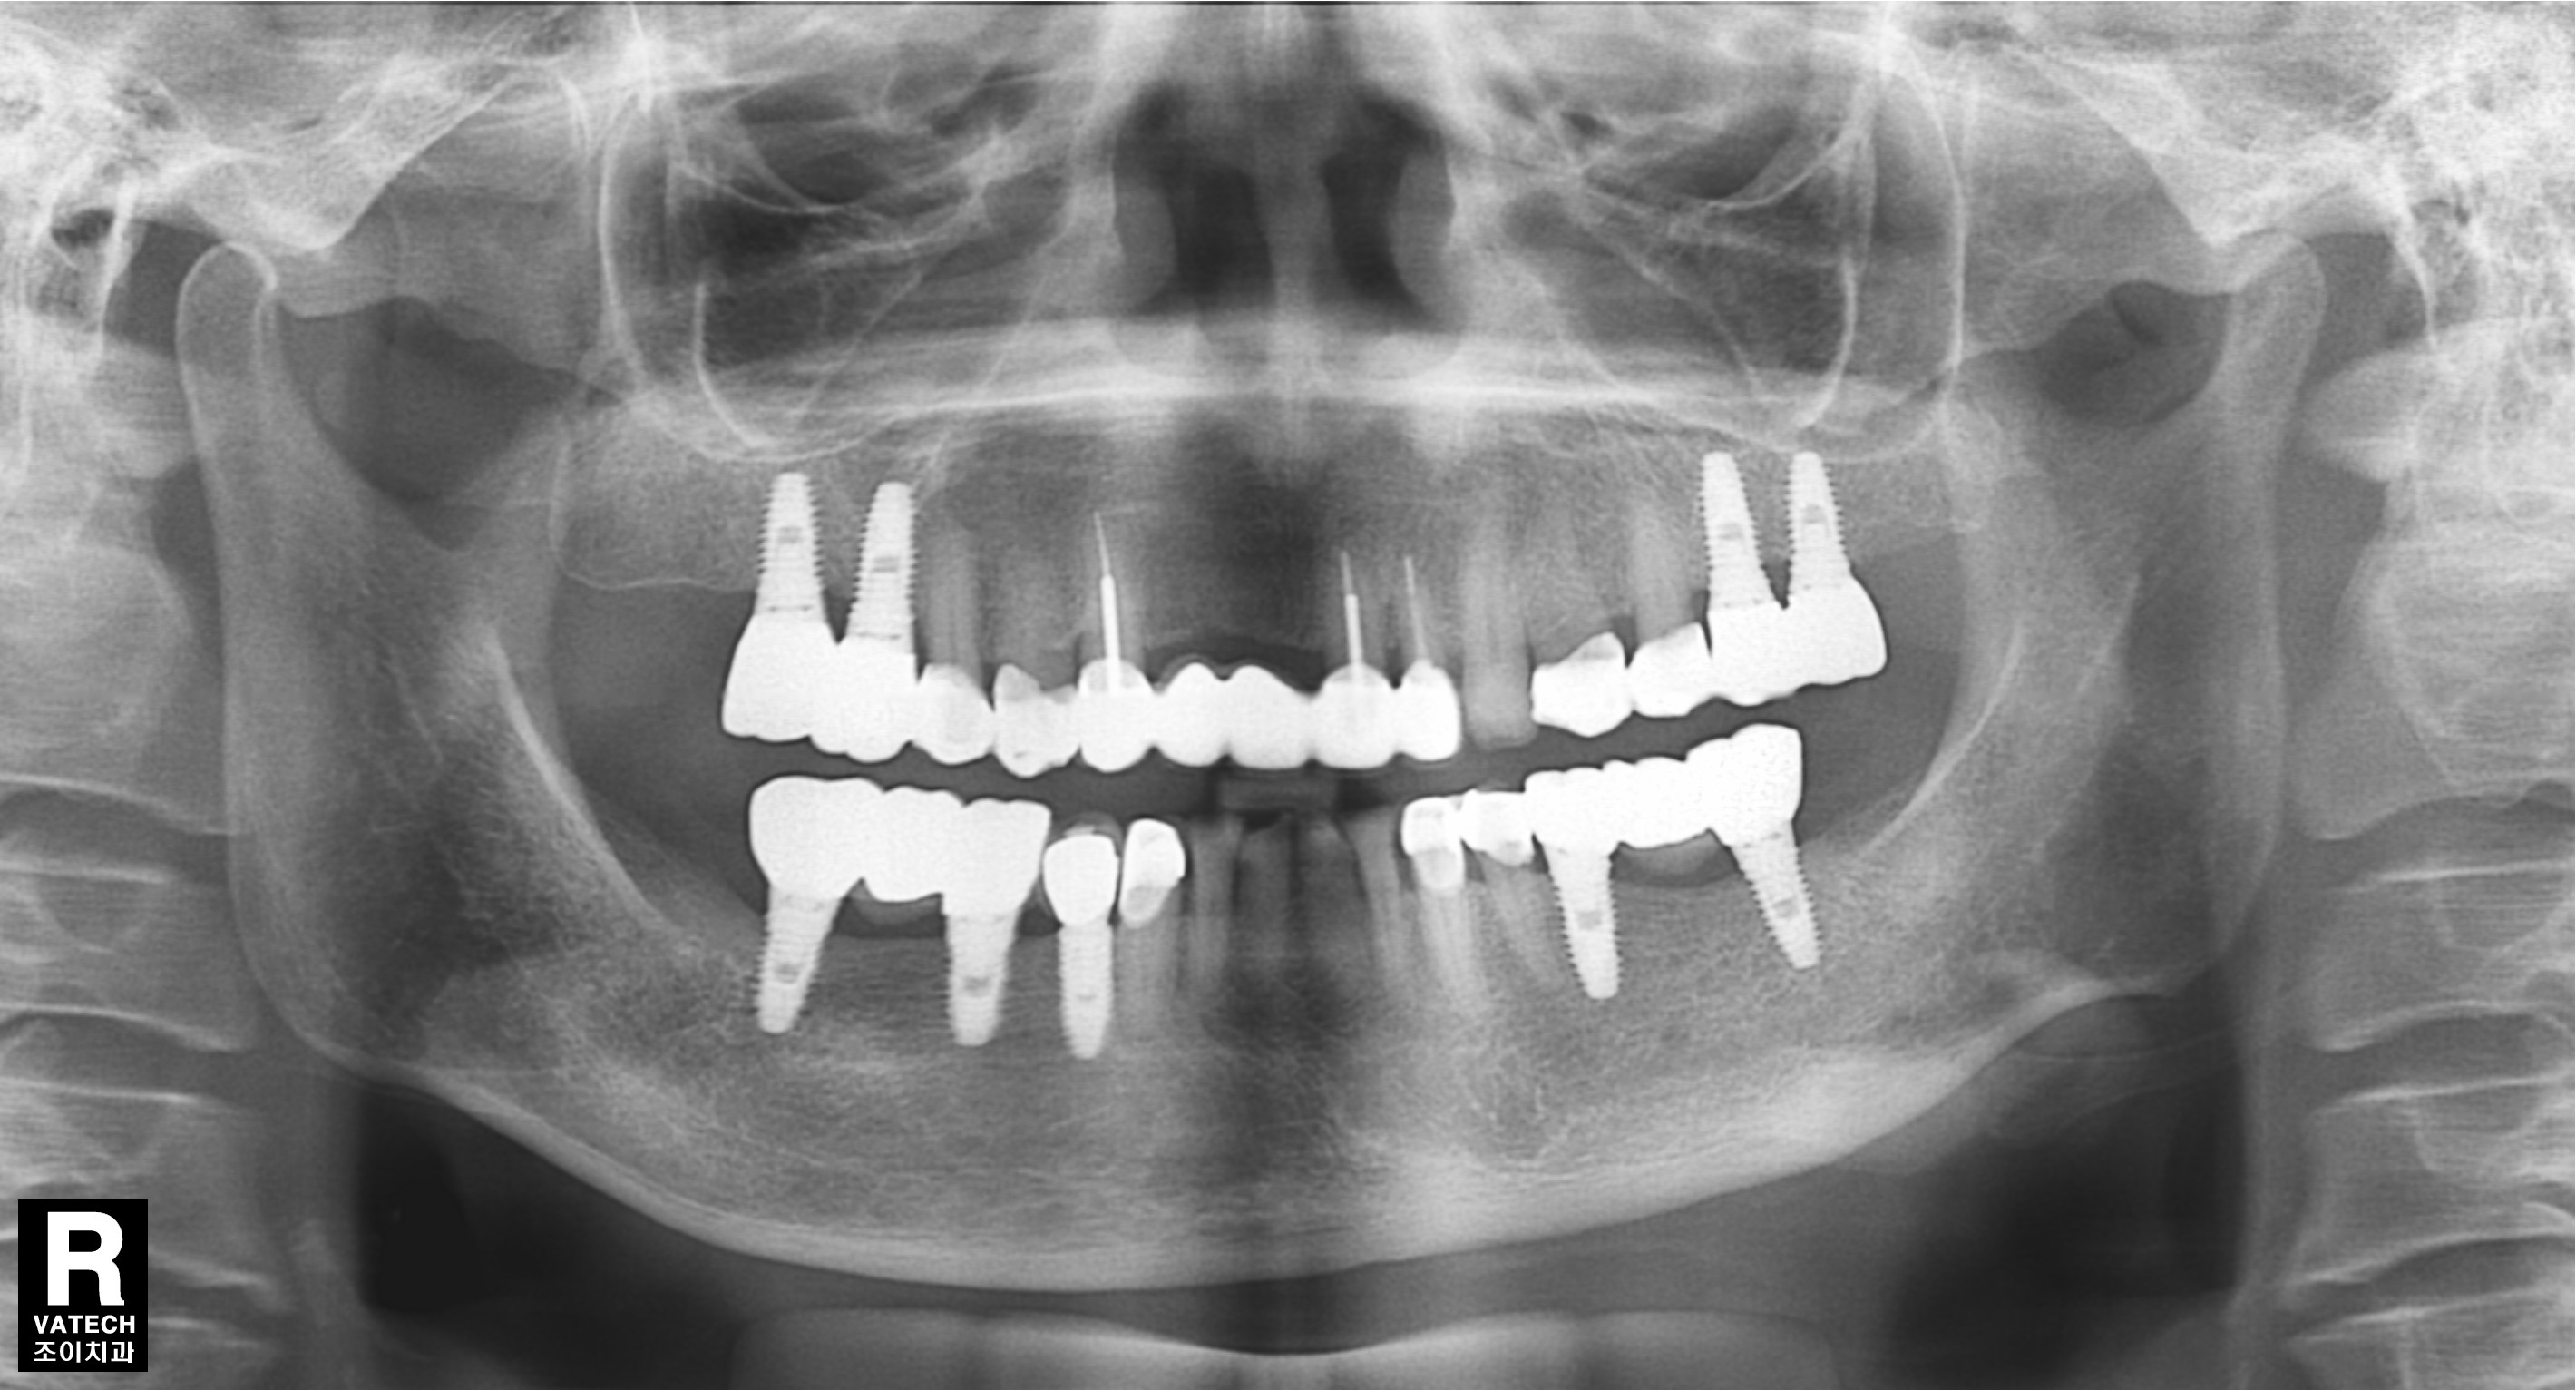

초진과 임플란트 보철 완성 직후 그리고 7년 경과 후 사진의 비교입니다.

또한 임플란트의 사용과 유지 관리에 있어서도 반드시 정기적으로 치과를 방문하여 적절한 관리를 받아야 합니다. 사진에서는 7년이 경과한 후에도 치조골의 흡수 없이 잘 유지되고 있는 상태를 관찰할 수 있습니다.

앞으로도 장기간 문제될 가능성은 거의 없어 보이는 경우입니다.